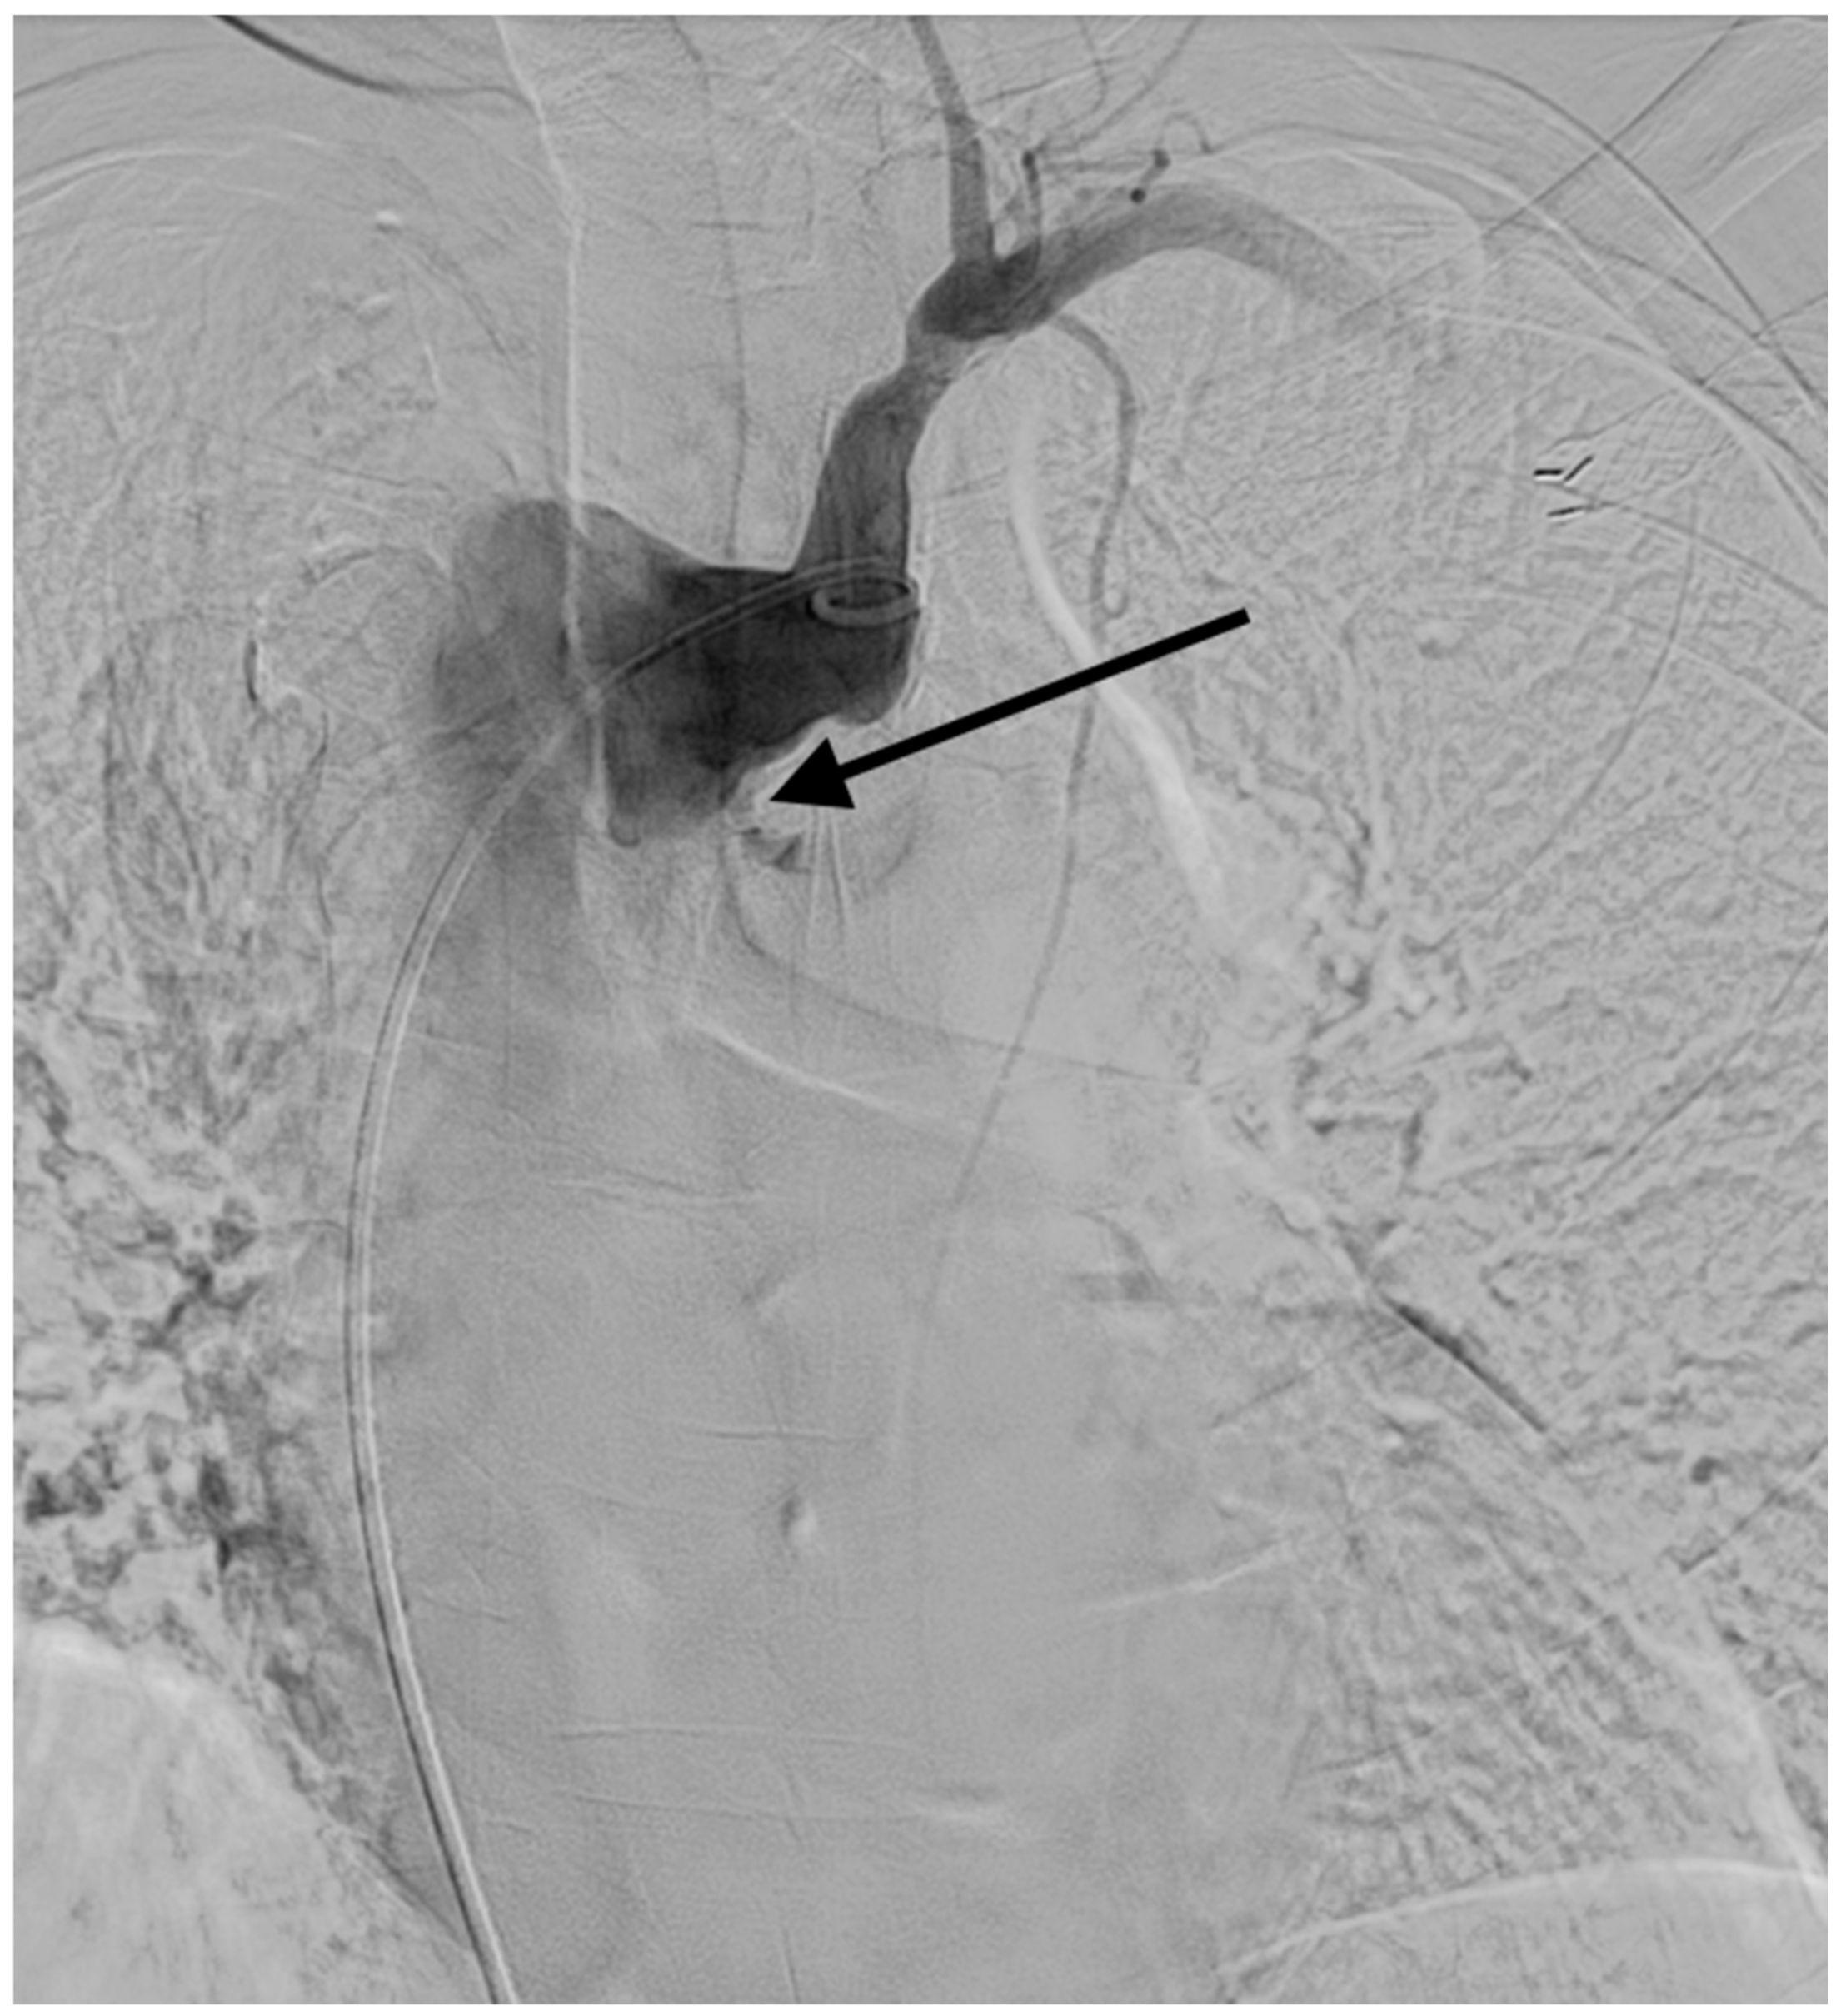

2. Case Report